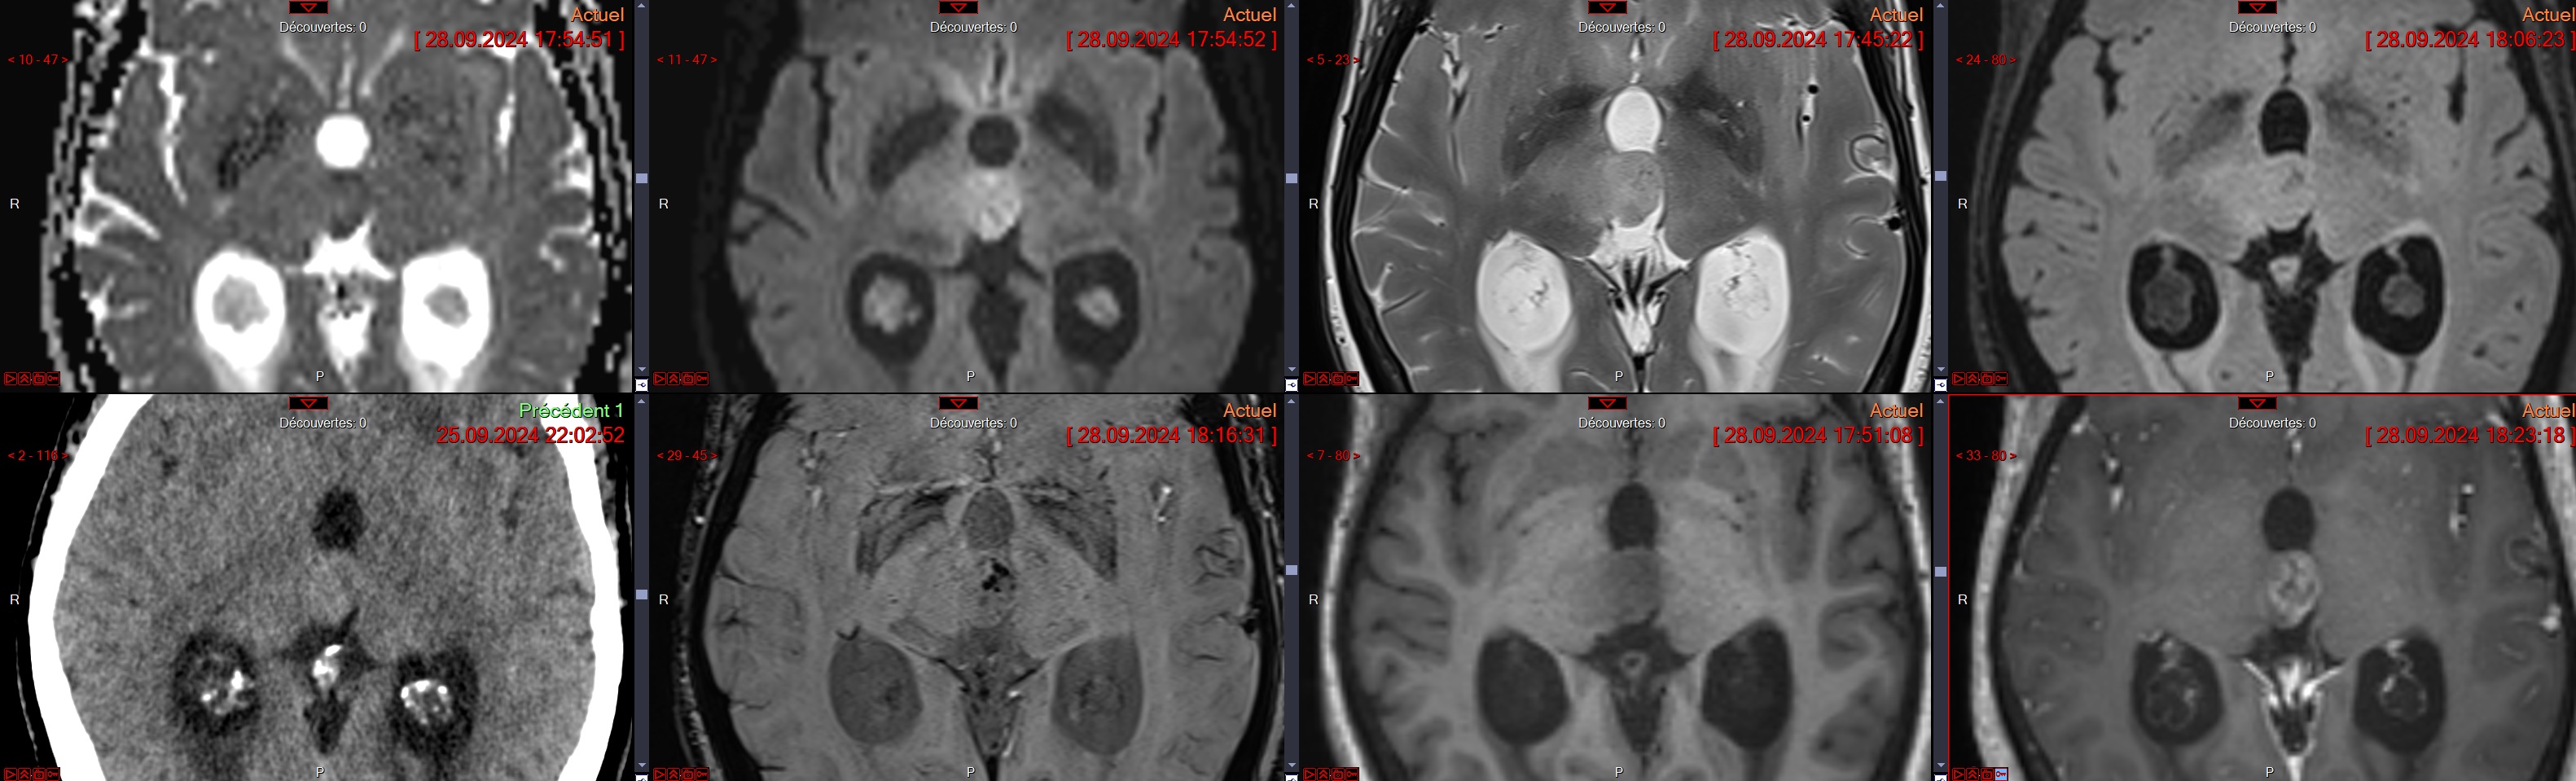

Cas

Glioblastome

Decouverte fortuite aux urgences, Confirmé a la patho

Decouverte fortuite aux urgences, Confirmé a la patho